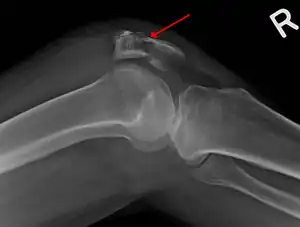

- Osteochondral fracture of patella

The patella can break in various ways depending on the way it is injured, and into two or more pieces.[1] Types include transverse, with one fracture line and is the most common type,[5] marginal, osteochondral and the rare vertical type, or stellate, where a direct compression force gives rise to a comminuted pattern.[5][7] Patella fractures can be further classified as displaced, where the broken ends of bone do not line up correctly and separate by more than 2mm, or undisplaced and stable where pieces of bone remain in contact with each other.[1][7] If fragments of patella bone stick out from the skin it is known as an open patella fracture, and closed if the overlying skin is intact.[1]